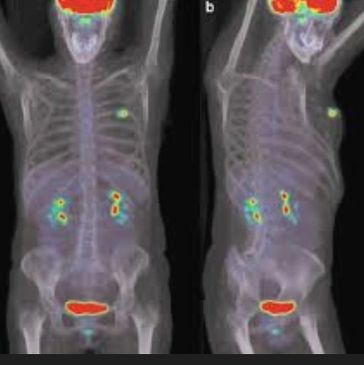

Principle: ^18F-FDG accumulates in metabolically active tumor tissue; fused PET–CT provides metabolic and anatomical correlation.

Indications:

Advantages:

Limitations:

Performance:

Clinical Value: